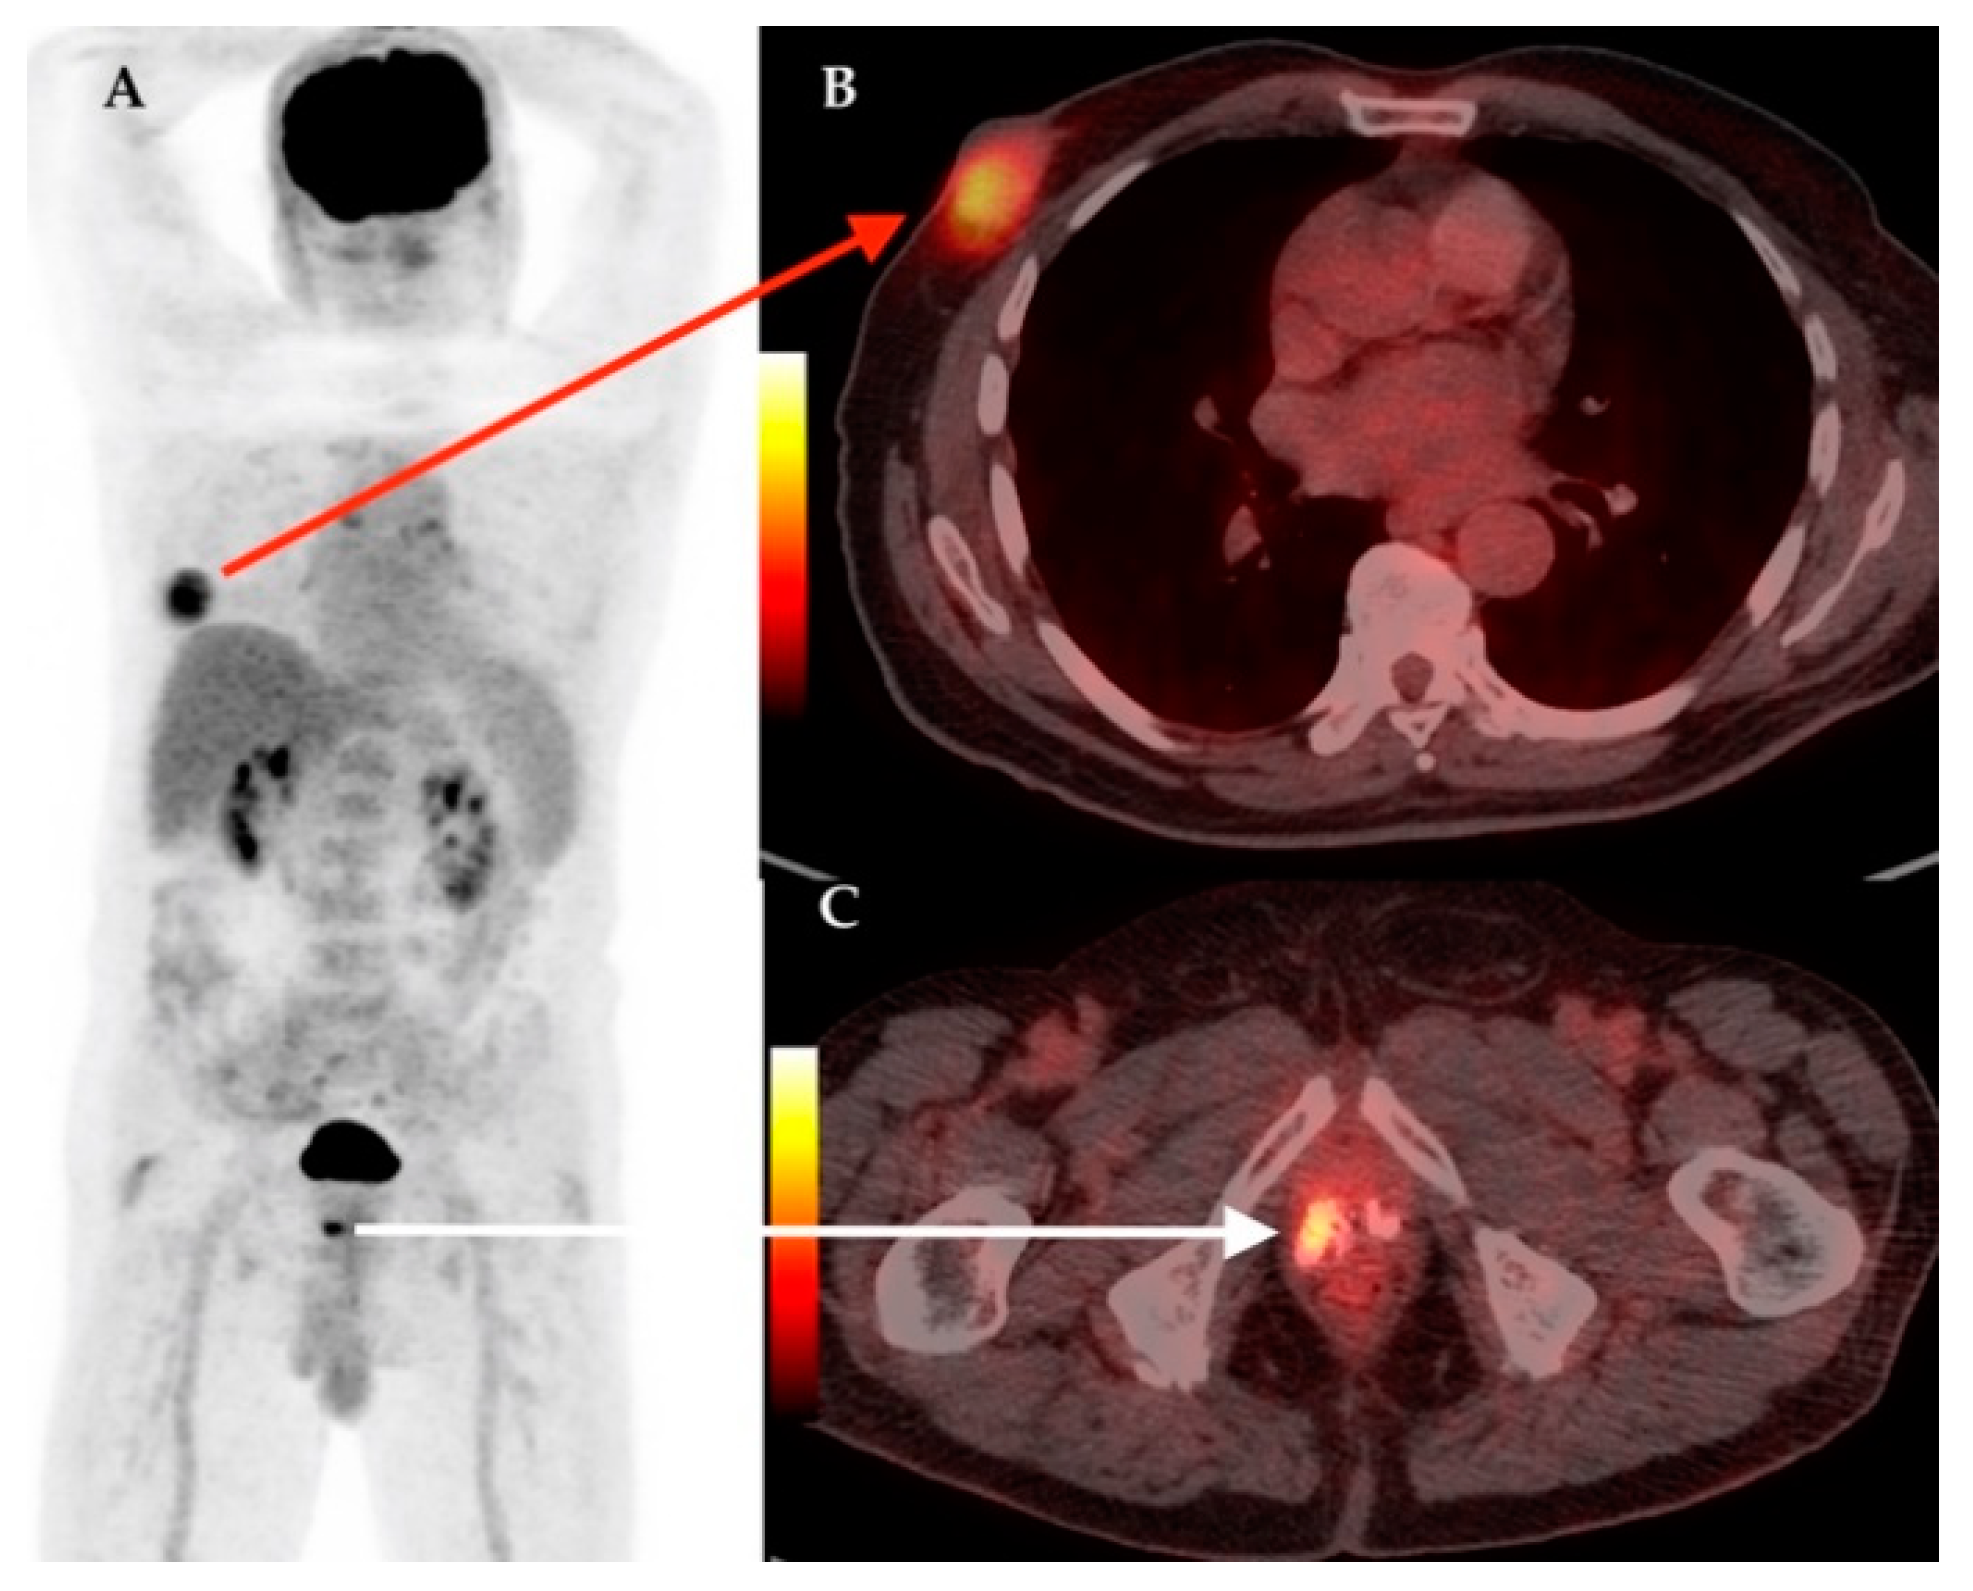

| 5 | 70 | IDC | RM + ALND | – | – | IB | – | Lu, Su | 3.37 | Colon cancer | 5.27 |

| 21 | 61 | IDC | RM + ALND | Yes | Yes | IIC | LN | – | 2.38 | Thyroid cancer | 23.1 |